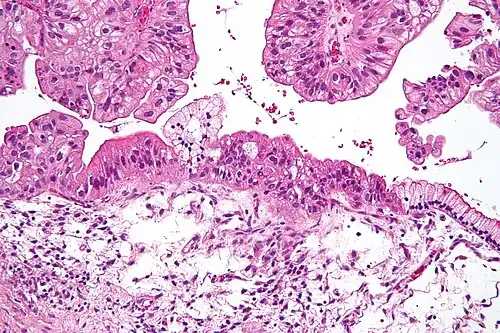

Ovarian mucinous tumor

Benign mucinous tumors are typically multilocular (have several lobes), and the cysts have a smooth lining of epithelium that resembles endocervical epithelial cells with small numbers of gastrointestinal-type epithelial cells. Borderline and malignant mucinous tumors often have papillae and solid areas. There may also be hemorrhage and necrosis.

Cystadenocarcinomas (malignant tumors) contain a more solid growth pattern with the hallmarks of malignancy: cellular atypia and stratification, loss of the normal architecture of the tissue, and necrosis. The appearance can look similar to colonic cancer.

Clear stromal invasion is used to differentiate borderline tumors from malignant tumors.